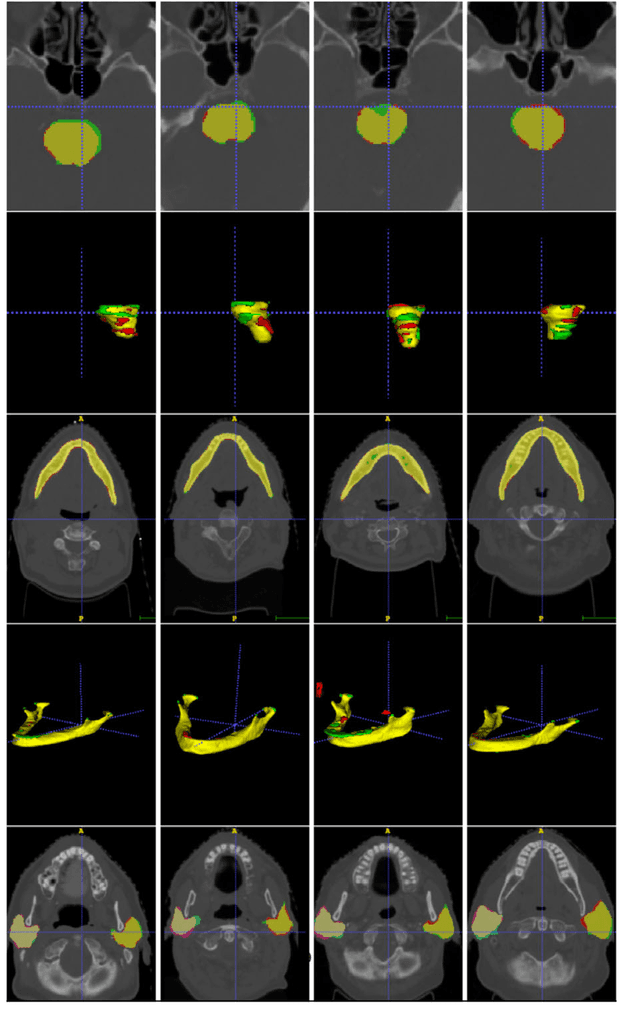

Abstract:Radiation therapy (RT) is a common treatment for head and neck (HaN) cancer where therapists are often required to manually delineate boundaries of the organs-at-risks (OARs). Automated head and neck anatomical segmentation provides a way to speed up and improve the reproducibility of radiation therapy planning. In this work, we propose the AnatomyNet, an end-to-end and atlas-free three dimensional squeeze-and-excitation U-Net (3D SE U-Net), for fast and fully automated whole-volume HaN anatomical segmentation. There are two main challenges for fully automated HaN OARs segmentation: 1) challenge in segmenting small anatomies (i.e., optic chiasm and optic nerves) occupying only a few slices, and 2) training model with inconsistent data annotations with missing ground truth for some anatomical structures because of different RT planning. We propose the AnatomyNet that has one down-sampling layer with the trade-off between GPU memory and feature representation capacity, and 3D SE residual blocks for effective feature learning to alleviate these challenges. Moreover, we design a hybrid loss function with the Dice loss and the focal loss. The Dice loss is a class level distribution loss that depends less on the number of voxels in the anatomy, and the focal loss is designed to deal with highly unbalanced segmentation. For missing annotations, we propose masked loss and weighted loss for accurate and balanced weights updating in the learning of the AnatomyNet. We collect 261 HaN CT images to train the AnatomyNet for segmenting nine anatomies. Compared to previous state-of-the-art methods for each anatomy from the MICCAI 2015 competition, the AnatomyNet increases Dice similarity coefficient (DSC) by 3.3% on average. The proposed AnatomyNet takes only 0.12 seconds on average to segment a whole-volume HaN CT image of an average dimension of 178x302x225.